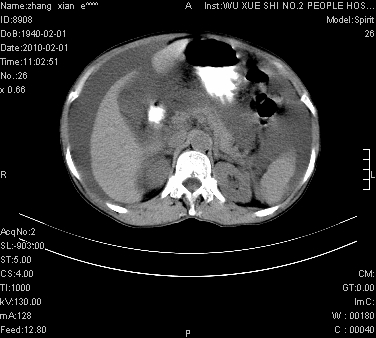

标题: CT24434:70岁 女 腹胀,腹水原因待查 [打印本页]

标题: CT24434:70岁 女 腹胀,腹水原因待查

大量腹水,脾脏囊性占位,子宫颈占位,右侧腹股沟淋巴结肿大,建议+c,先查妇科。

腹盆腔大量积液,子宫增大,子宫颈增大外形不规则,内见低密度影,膀胱后壁显示不清,右腹股沟肿大淋巴结,脾脏囊性占位,子宫颈占位,子宫颈癌?建议增强。

考虑:1、腹膜转移,大量腹水;

2、脾占位性病变;

3、左侧卵巢占位性病变,建议增强进一步检查。

大量腹水,右肾、脾囊肿可能性大          考虑左侧附件区占位,建议增强